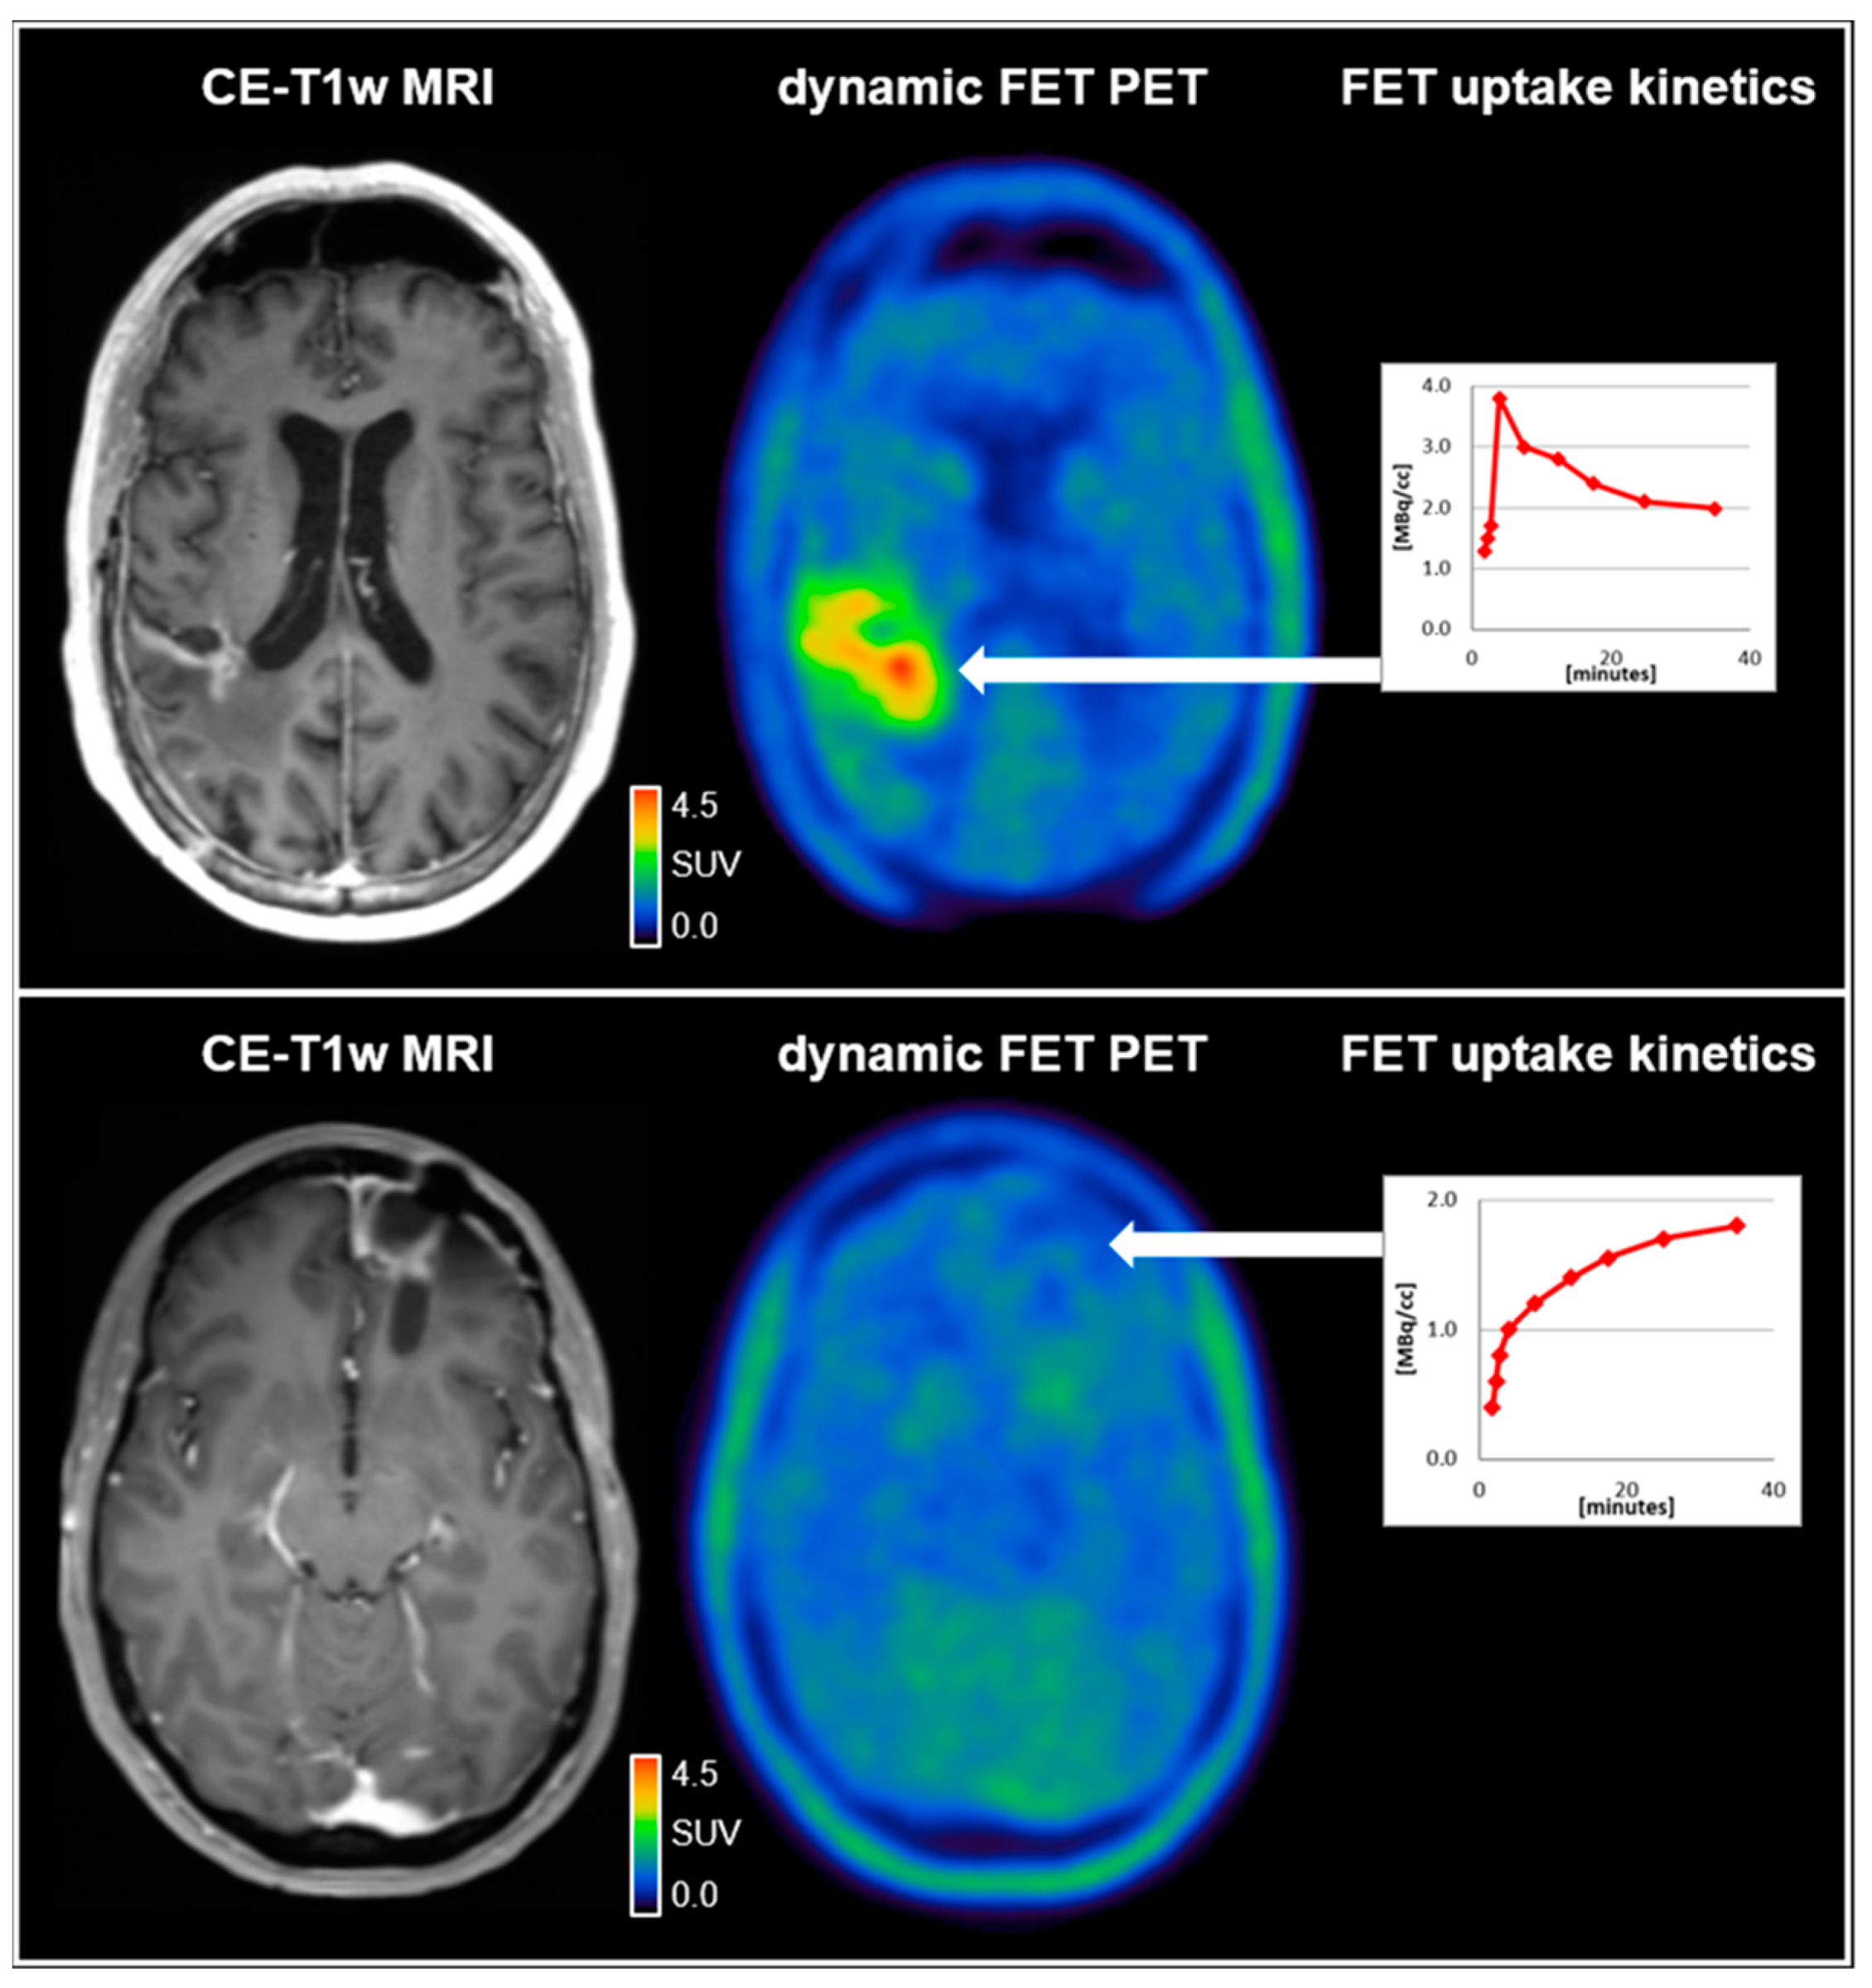

Amino acid uptake in both glioma and brain metastases is provided by large amino acid transporters (LAT) and has been shown to correlate with the density of LAT expression on the cell membrane surface in both entities [10]. In recent years, the relevance of AA-PET in the brain and spinal lesions has increased due to more refined imaging and postprocessing methods [2]. While the calculation of intralesional uptake relative to the healthy brain tissue, referred to as tumor-to-brain ratio (TBR), remains the standard in most centers, the analysis of tracer uptake dynamics is gaining further importance as it has been shown to enhance the diagnostic accuracy [11]. A reliable measurement of tracer uptake dynamics has predominantly been established for 18F-FET and, more recently, also for 18F-FDOPA [12]. For quantitative data analysis, mainly the dynamic parameters slope and time-to-peak (TTP) are calculated from time–activity curves (TAC). In glioma patients, dynamic parameters have been shown to correlate with the tumor grade according to older classification systems and, moreover, to molecular markers, such as mutations of the isocitrate dehydrogenase (IDH) gene [13,14]. Additionally, this technique allows differentiating between tumor progression and treatment-related changes in patients with glioma and brain metastases with high diagnostic accuracy [15,16]. An example illustrating the value of dynamic 18F-FET PET parameters for the differentiation between treatment-related changes and glioblastoma relapse is shown in Figure 1.

Figure 1.

(upper row) A 59-year-old male patient diagnosed with an IDH-wild-type glioblastoma (WHO CNS grade 4). Following resection and chemoradiation with temozolomide, the contrast-enhanced MRI (CE-T1w MRI) suggested tumor relapse in the right parietal region 7 months after completing radiotherapy. Accordingly, the dynamic FET PET scan revealed pathologically increased FET uptake right parietal (TBRmax, 4.2) and decreased time–activity curve; (lower row). A 37-year-old female patient diagnosed with an IDH-wild-type glioblastoma (WHO CNS grade 4). Following resection and chemoradiation with temozolomide, the contrast-enhanced MRI suggested tumor relapse in the left frontal region 7 months after completing radiotherapy. In contrast to the patient in the upper row, the FET uptake in the left frontal region was not pathologically increased (TBRmax, 1.6) with a steadily increasing time–activity curve, indicating reactive treatment-related changes. SUV = standardized uptake value.